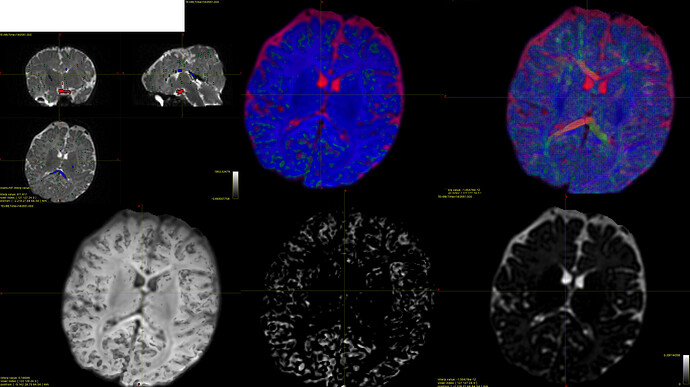

I think the response functions from dwi2response dhollander look good, but I’m concerned about the FODs.

The FODs generated in the next step look a bit strange to me and don’t look like the example in Andy’s tutorial. As you can see, it looks like there is very little gray matter (top middle image; all of the participants look like this, with very little green). I used SS3T from MRtrix3Tissue and then overlaid the WM FODs on top of the combined image (top right image). Again, this image also does not look like the one from the tutorial.

The bottom row has the individual FODs for each tissue type (WM, GM, CSF):

I apologize for uploading them all as one image—it seems like as a ‘new user’ I can only include one attachment in my post, so I wasn’t able to attach each photo individually at this time.